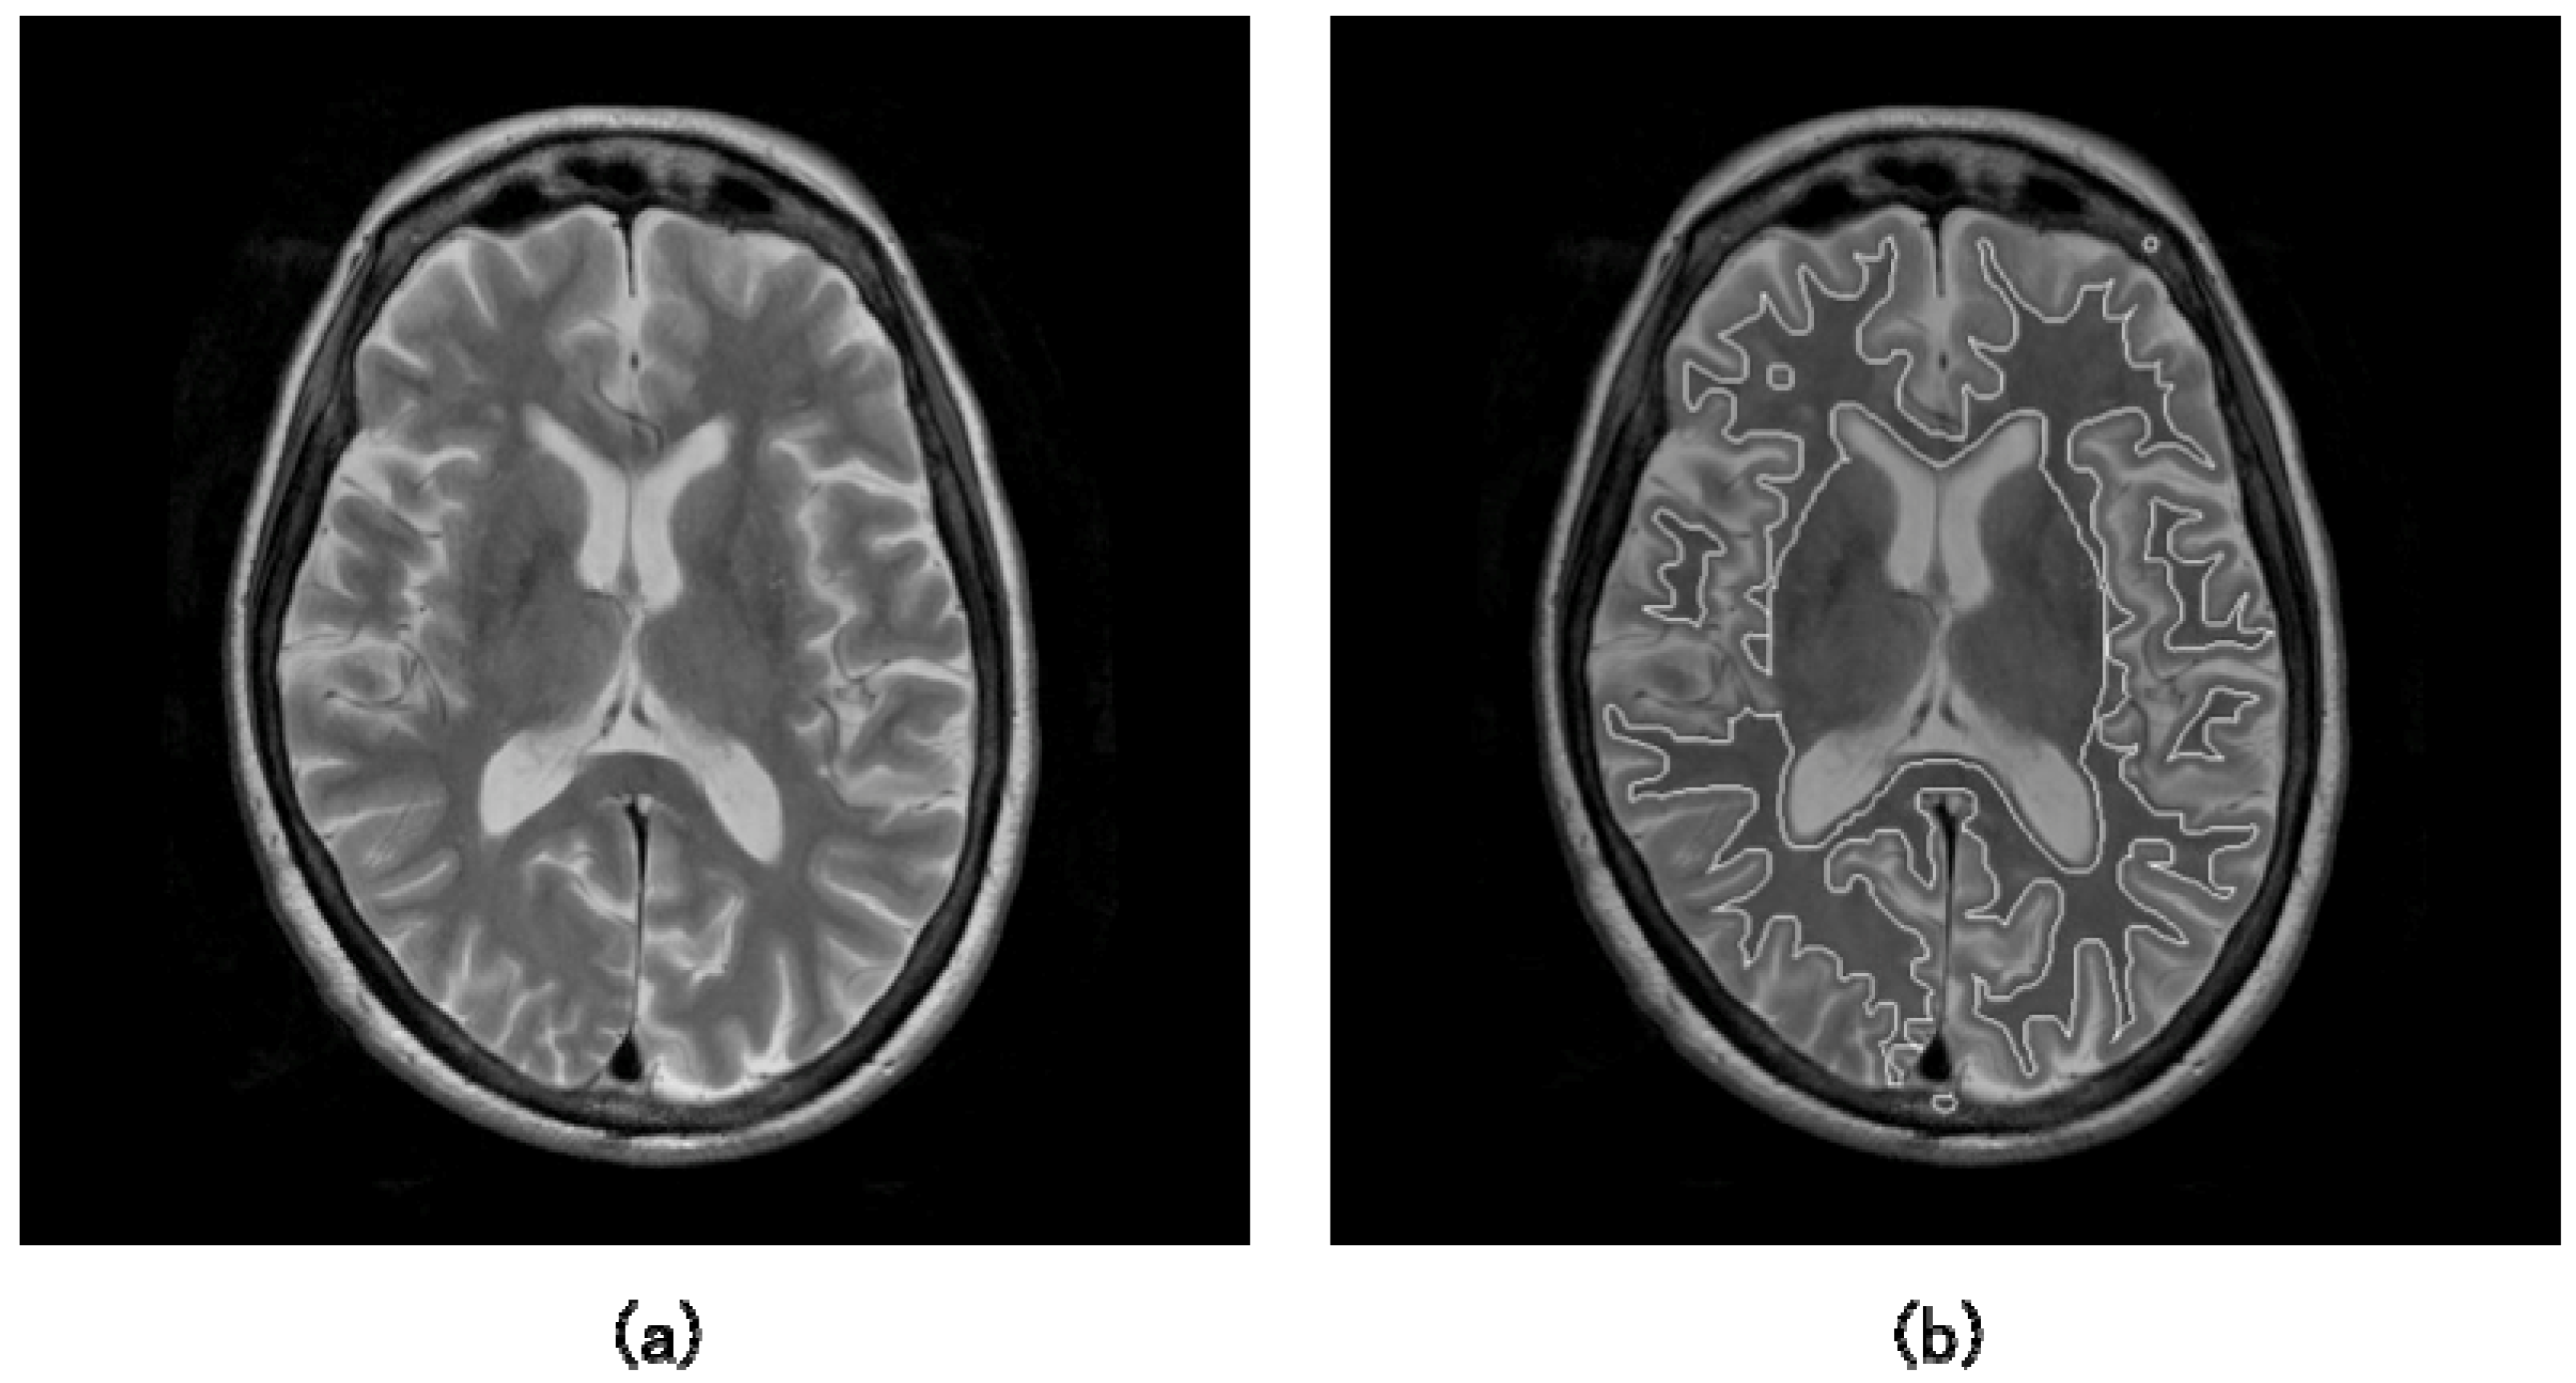

where t is the time and F is the speed function. While updating the level set function, the zero level set ϕ = 0 moves according to the speed function in the higher dimensional level set function. Here, the zero level set is called as “moving front”. Finally, the update of the level set function was stopped if some conditions are satisfied. Figures 7(a) and 7(b) show the illustrations of an original T2-weighted image and white matter regions segmented by a level set method, respectively [55].

Figure 7.

Illustrations of: (a) an original T2-weighted image and (b) white matter regions segmented by a level set method [55].

Figure 13 shows the segmentations of brain regions (outer white line) and white matter regions (inner white line) obtained by the proposed method from a non-AD patient in multiple coronal planes. As a result, the area under a ROC curve (Az value) obtained by the CAD system was 0.909 based on a leave-one-out test in identification of AD patients among 54 cases. The preliminary results showed that the proposed method may be promising for identification of AD patients.

Figure 13.

Segmentations of brain regions (outer white line) and white matter regions (inner white line) obtained by the proposed method from a non-AD patient in multiple coronal planes [27].